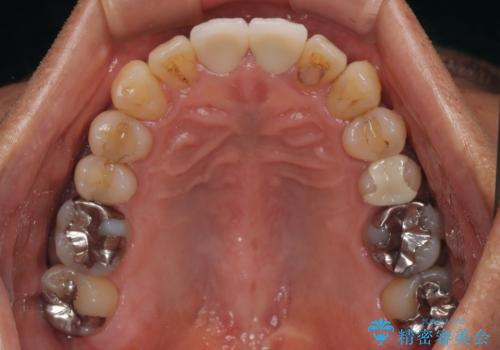

左右対称の2本の歯にセラミッククラウンを装着したことで、調和の取れた審美的な口元となりました。